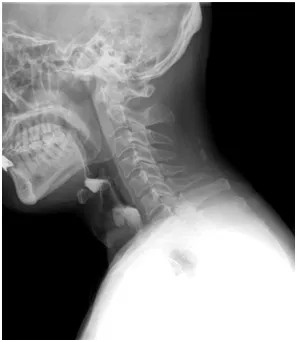

张奶奶来到郑州大学第五附属医院后,康复医学科吞咽治疗团队为她的病情做了详细评估,充分评估脑梗死及其他相关慢性疾病的严重程度,详细了解张奶奶吞咽困难出现的时间、进展情况、伴随症状等信息,并进行专业吞咽评估检查,如洼田饮水试验、吞咽造影检查等。

▲ 吞咽造影检查